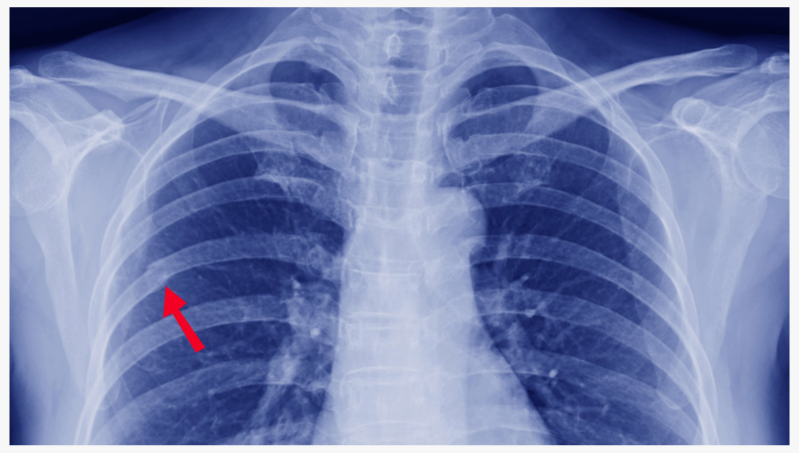

Привозят дедушку, 80 лет. Жалуется на боль в грудной клетке, одышку, сатурация — около 80%. Предварительный диагноз скорой помощи: пневмония. Всё вроде бы логично. Пока не начинаешь внимательный осмотр. Температуры — нет, кашля — нет. Перкуссия грудной клетки — и слышим.. подозрительный хруст (мы зовём его крепитацией)🤔

КТ органов грудной клетки — и вот он, “сюрприз” - перелом ребра и пневмоторакс. Не пневмония, а опасная❗травма. Пациент экстренно переводится по профилю.

👇 Изображение КТ: стрелка указывает на место перелома.

Пример перелома ребра на КТ ОГК. Источник: радиологичнеский атлас.